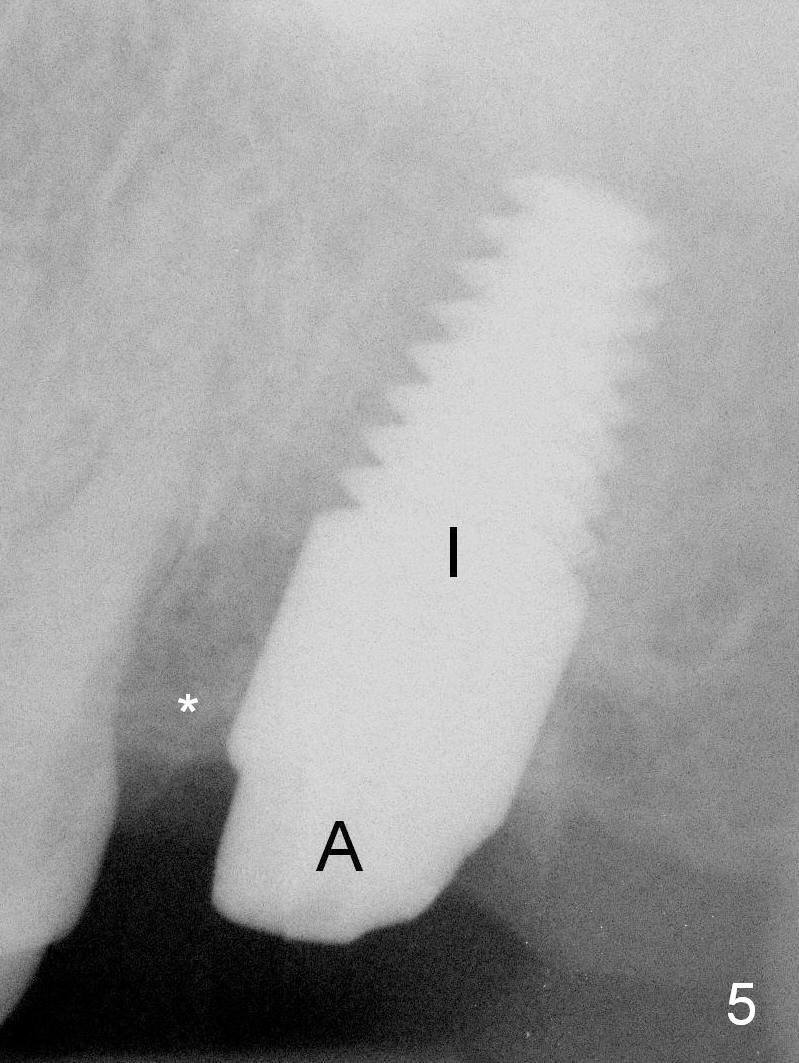

A 6x14 mm implant (Fig.5 I) and a 5x3 mm abutment (A) are placed. After abutment height adjustment, an immediate provisional is fabricated. Allograft with Osteogen is placed in the remaining sockets and gaps. Insertion torque of the implant is > 56 Ncm. The mesial crest is low in density (*).